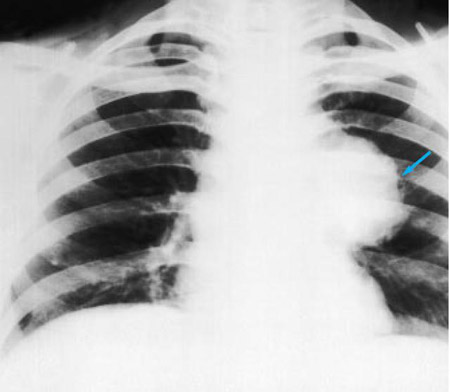

Uma radiografia torácica deve ser obtida no início da avaliação da tosse crônica.[38] Embora não seja diagnóstica das causas mais comuns, os achados podem facilmente desviar a avaliação para causas de maior gravidade como doenças pulmonares estruturais. Eles incluem câncer pulmonar, fibrose pulmonar, tuberculose, bronquiectasia, pneumonia, aspiração e sarcoidose.[Figure caption and citation for the preceding image starts]: Radiografia torácica mostrando hiperinsuflação em paciente com DPOC. A hiperinsuflação é causada pelo componente de enfisema na DPOC, em vez da bronquite crônica subjacente aos sintomas da tosseDo acervo pessoal do Dr. M. A. Sharifabadand, SUNY na Stony Brook School of Medicine, Departamento de Medicina Pulmonar e Intensiva, Mineola, Nova York, e Dr. J. P. Parsons, The Ohio State University Medical Center, Columbus; usado com permissão [Citation ends].

[Figure caption and citation for the preceding image starts]: Radiografia torácica mostrando carcinoma hilar esquerdo (seta)De: E. Dick, Student BMJ. 2000;8:358-360 [Citation ends].